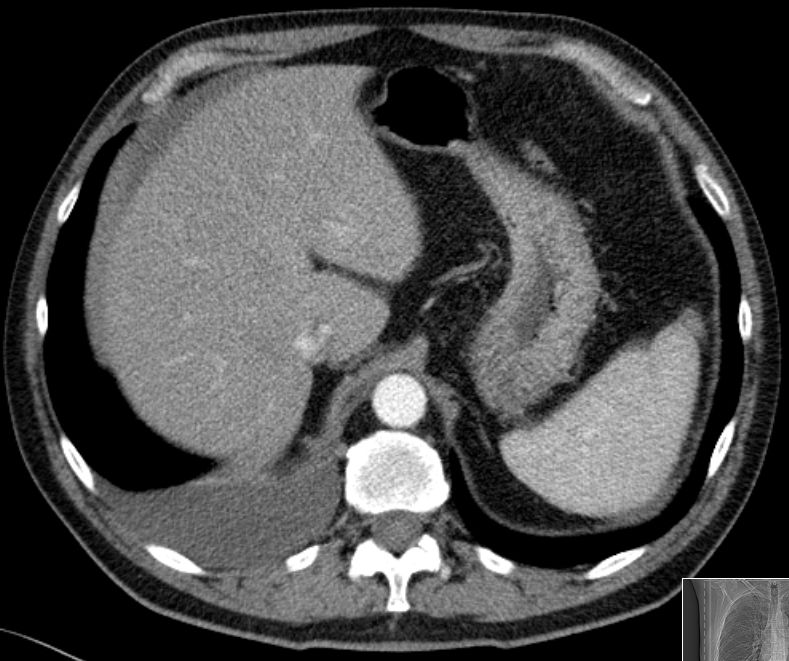

| Fallbeispiel | 63-jähriger Mann, bei dem ein rechtsseitiger Pleuraergusses auffiel.

Im Oberbauch ein schmaler Aszitesrand um die Leber erkennbar. Histologisch epitheloides Pleuramesotheliom mit Peritonealbefall (im CT nicht erkennbar).